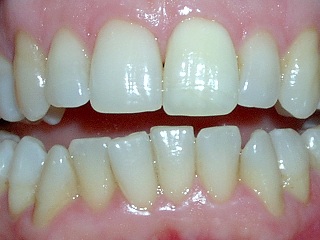

IL TUO DENTISTA VEDE ABBASTANZA?

Pare che Galileo ci vedesse bene ma pensate che avrebbe potuto studiare il sistema solare altrettanto bene senza l'aiuto del suo telescopio?

La larghezza reale di uno degli incisivi che vedi in foto è di circa 8 millimetri, all'interno di esso sono contenute strutture microanatomiche complesse che il tuo dentista deve vedere per poterle rispettare.

Pensi che sia più facile fare un buon lavoro vedendo con un ingrandimento 5 volte superiore?

Come puoi vedere nell'ingrandimento, tra i due incisivi è presente un notevole quantitativo di placca che non risulta visibile ad ingrandimento normale.

I tuoi denti sono preziosi, assicurati che vengano utilizzate tutte le tecnologie disponibili per salvaguardarli!